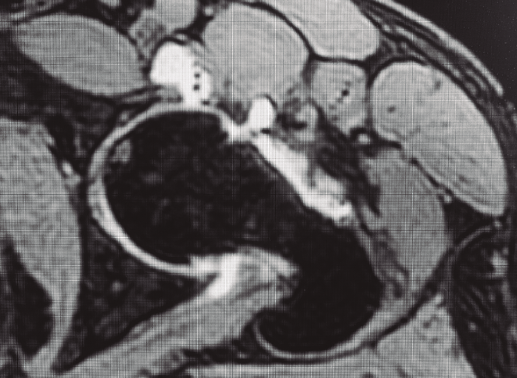

En lo referente al estudio mediante RM, se consideró la presencia de lesiones cartilaginosas de alto grado en espejo con edema subcondral, tanto en el acetábulo como en la cabeza femoral, como el signo más crítico y determinante de una enfermedad degenerativa avanzada. Se acordó que la lesión de un solo lado, acetabular o de cabeza femoral, con edema subcondral es importante, pero no tan crítica.

Figura 2. Paciente con geodas subcondrales acetabulares y en cabeza femoral, osteofito de contrachoque posteroinferior, espacios < 2 mm, incorrecta resección de CAM previo y defectos capsulares marcados.